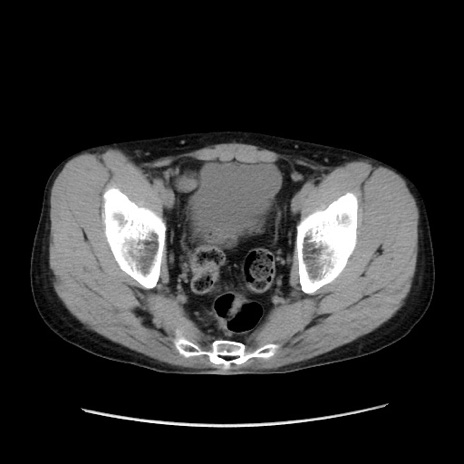

症例37(横断像)

【症例】40歳代 男性

【主訴】腹痛

【現病歴】4時間ほど前に電車に乗車中に臍部上より腹痛出現。徐々に増悪し起立困難となり、救急外来受診。生ものは数日食べていない。今朝お雑煮を食べた。

【身体所見】BT 36.8℃、BP 117/84mmHg、HR 91/min、SpO2 97%、苦悶様、腹部:臍上部広範囲圧痛あり、反跳痛±

【データ】WBC 8100、CRP 0.03